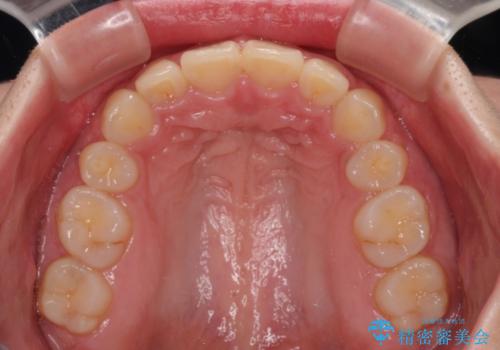

事前の予想通り、長期間を要する治療となりましたが、横顔の印象が劇的に変化し、患者様には大変満足していただきました。

- 飛び出した上顎前歯と、閉じにくい唇、口元の突出した印象の横顔を気にして来院された患者様です。

骨格的な上顎前突であり、上下前歯の前後的な距離が大きいため、上顎は左右第一小臼歯を、下顎は左右第二小臼歯をそれぞれ2本抜歯することで前歯が接触するようにし、さらには奥歯の咬み合わせも、より理想的な状態へ近づけていくこととしました。